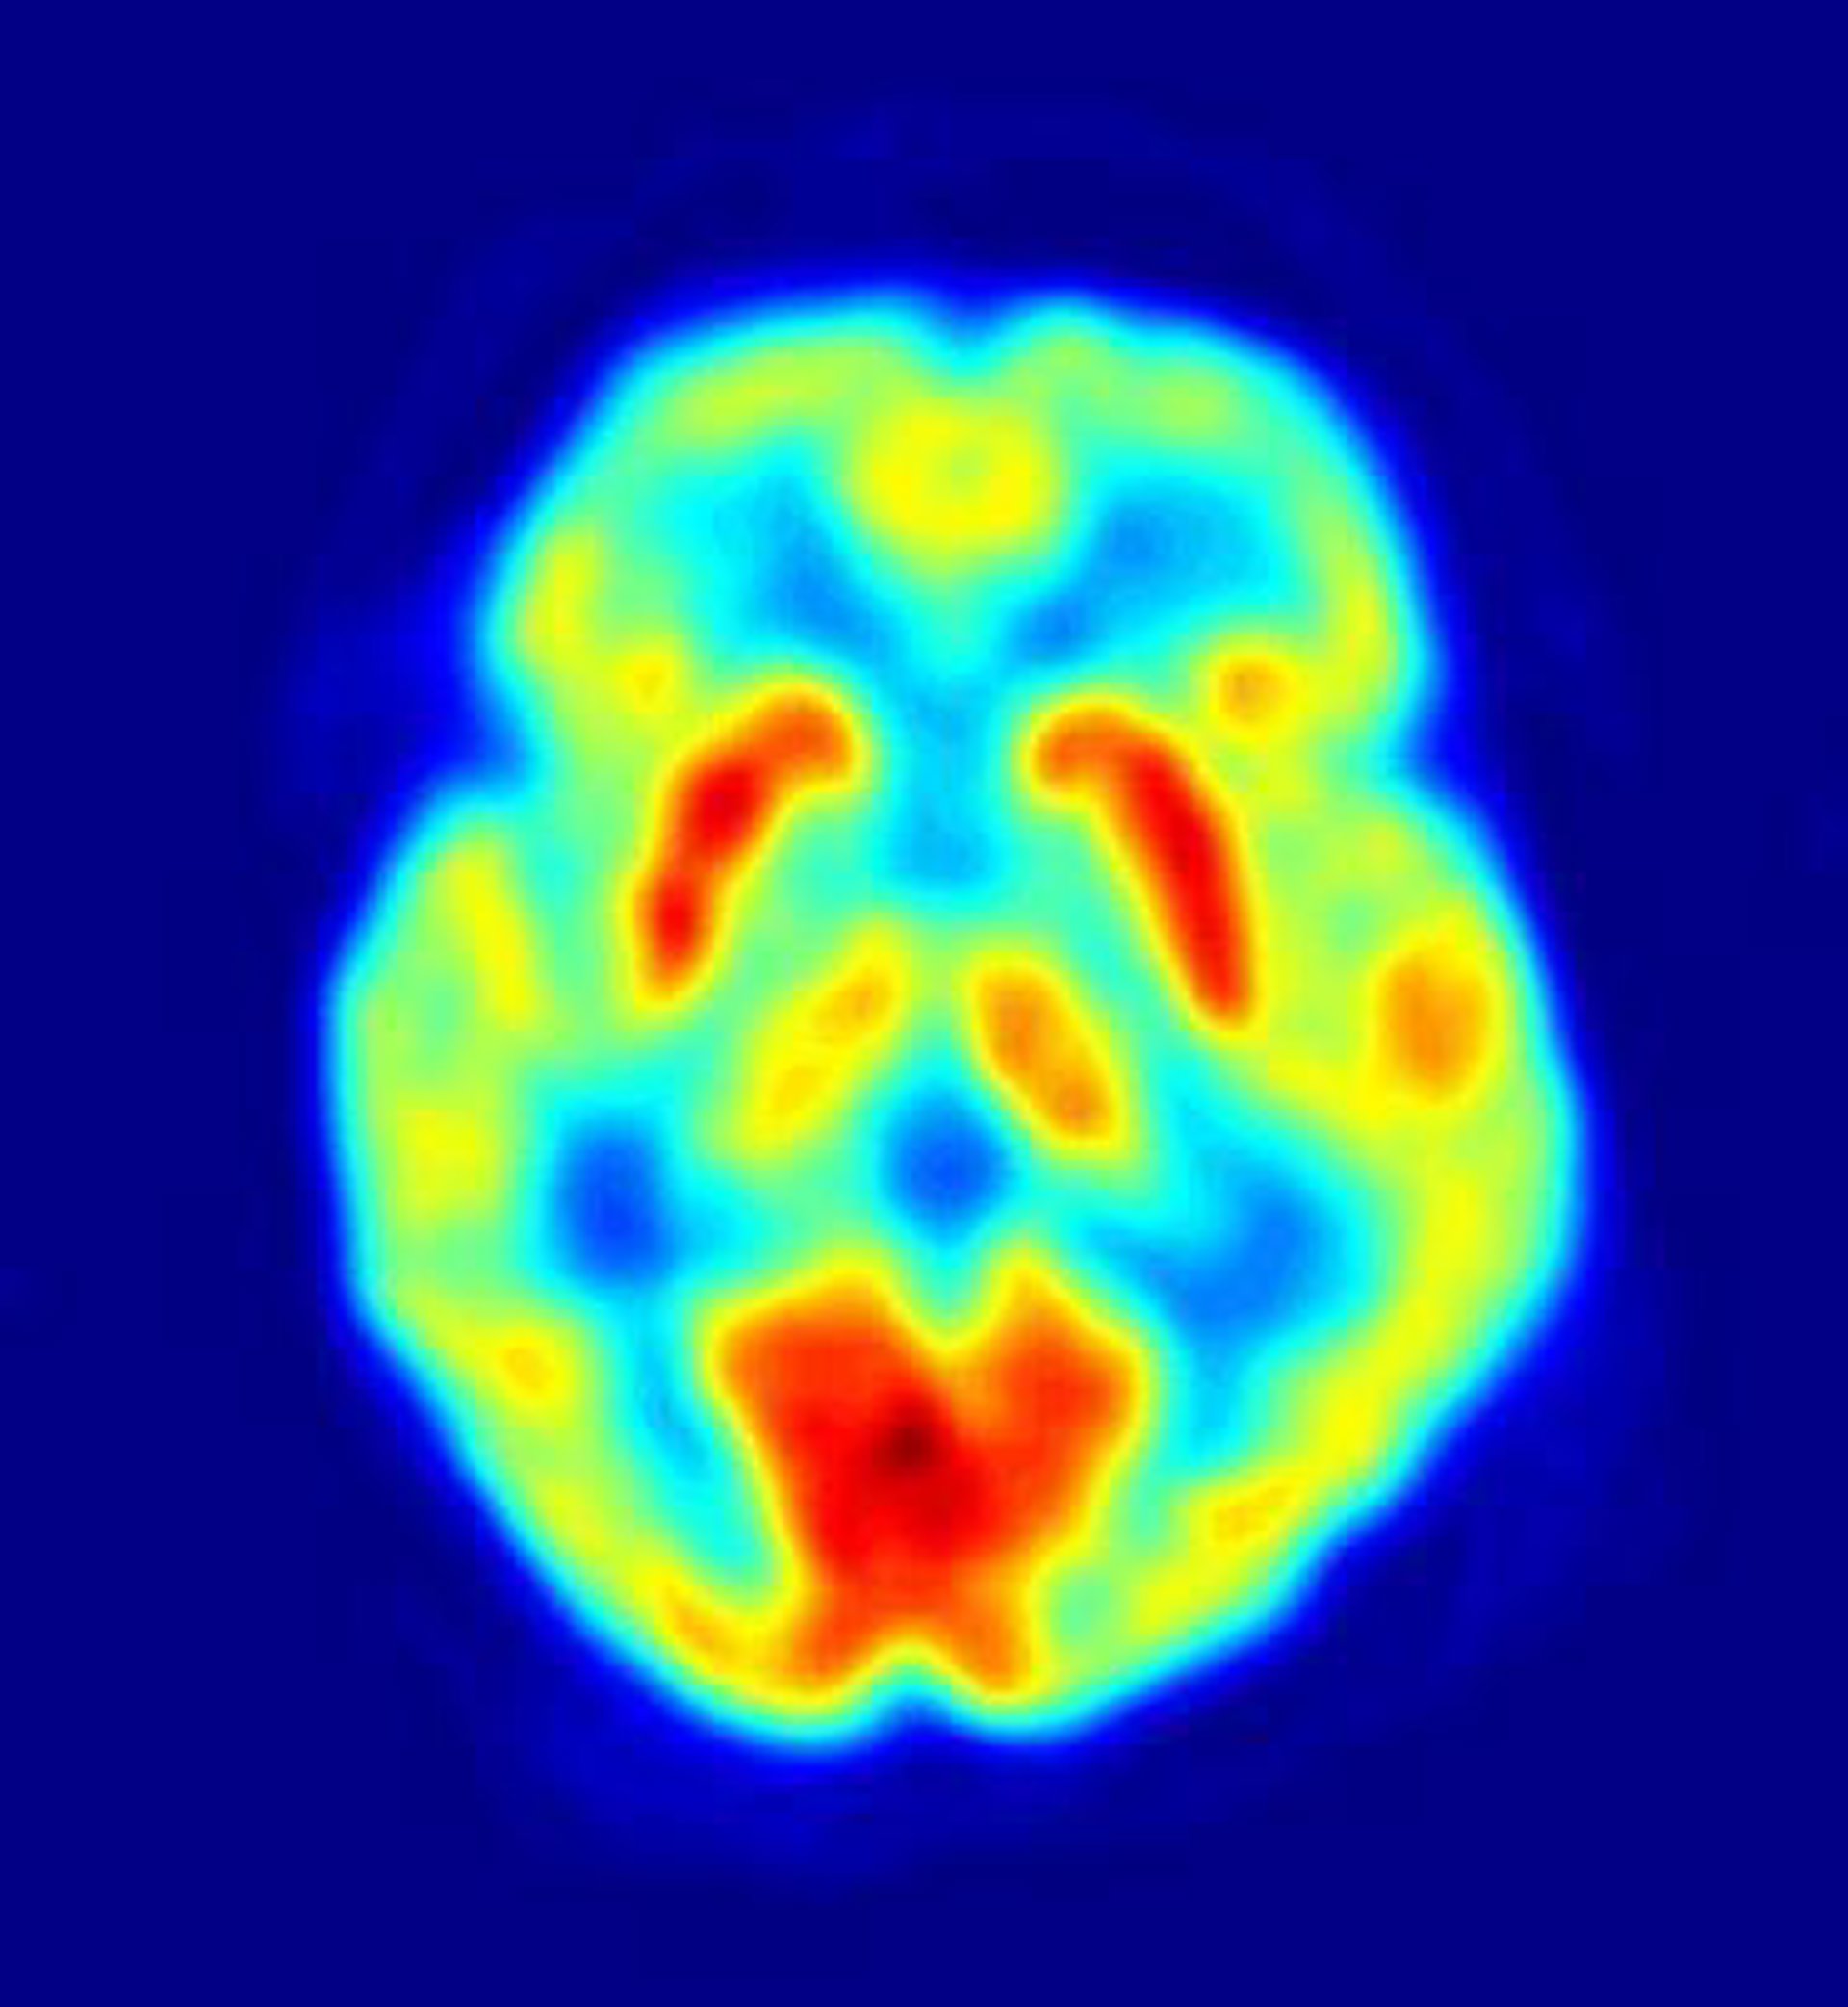

Cerebro

Wikimedia Commons